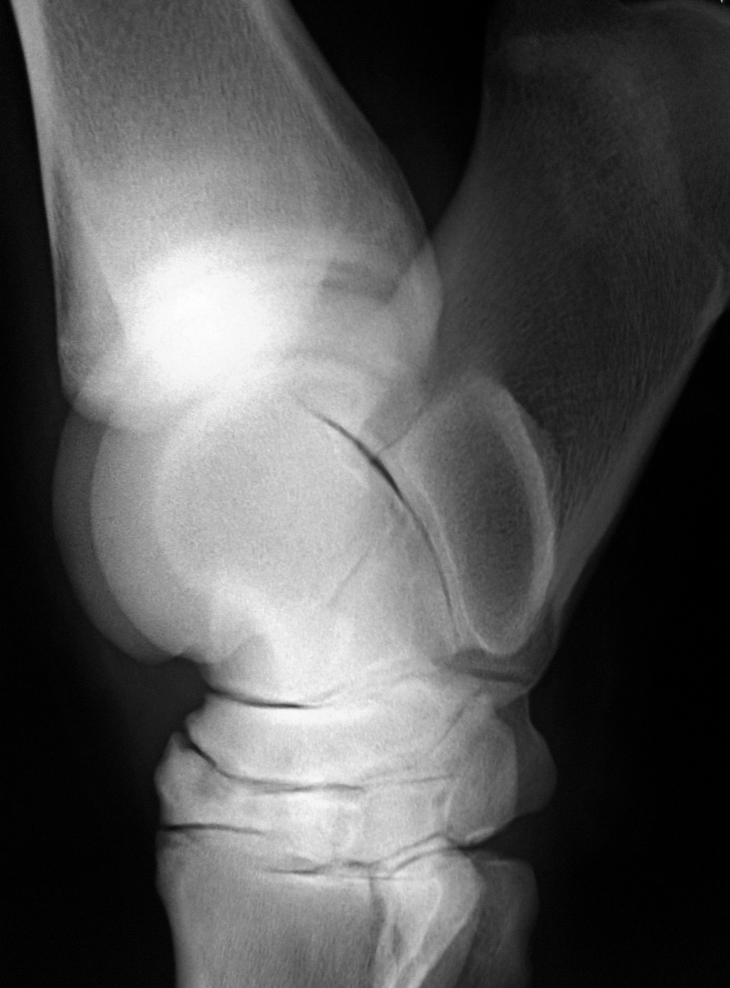

What are the common locations for stifle osteochondrosis?

-lateral trochlear ridge of femur (most common) -medial trochlear ridge of femur -articular surface of patella (worst prognosis) -medial femoral condyle (osseous cyst-like lesion) *often bilateral*

What is shown in this image?

osteochondrosis lesion on lateral trochlear ridge of femur

27